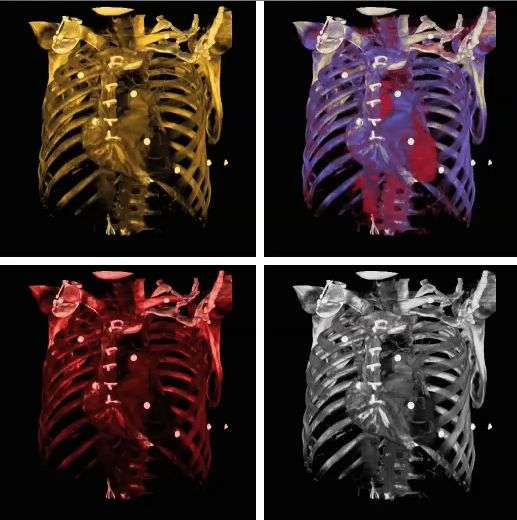

Note also that the colour look-up table (CLUT) can be varied to highlight features of particular interest, as shown in the set of images below: